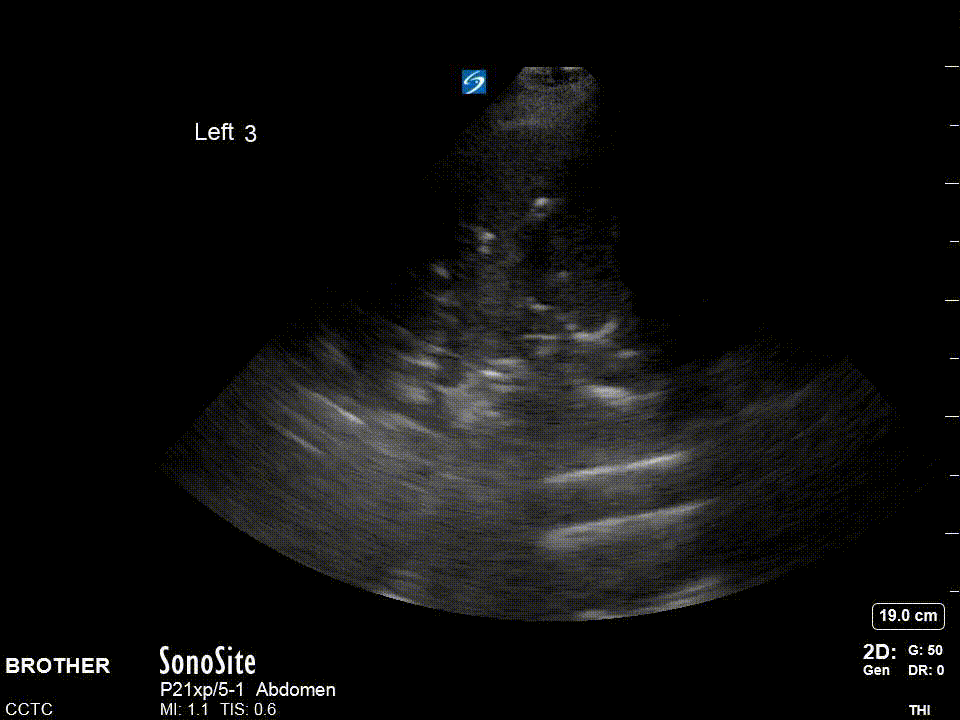

For the diaphragm/lung base views R3 and L3 the ideal view should include as much of the diaphragm as possible, the liver or spleen, and the vertebral column. You generally have to be quite posterior, usually the mid-axillary, and potentially even posterior-axillary to achieve these views. Remember, in a normal, well-aerated lung you should not be able to see anything below the pleural line and as lung enters the view everything below will be “greyed out”; this effect is known as “curtain sign”.

The R4/L4 zone is to assess for the so called PLAPS or posterolateral alverolarpleural syndrome. This zone is posterior to the posterior axillary line and is intended to assess for retrocardiac/paraspinal pneumonia/atelectasis frequently missed by chest x-ray. The normal anatomy is lung curtaining screen left and liver/spleen screen right.